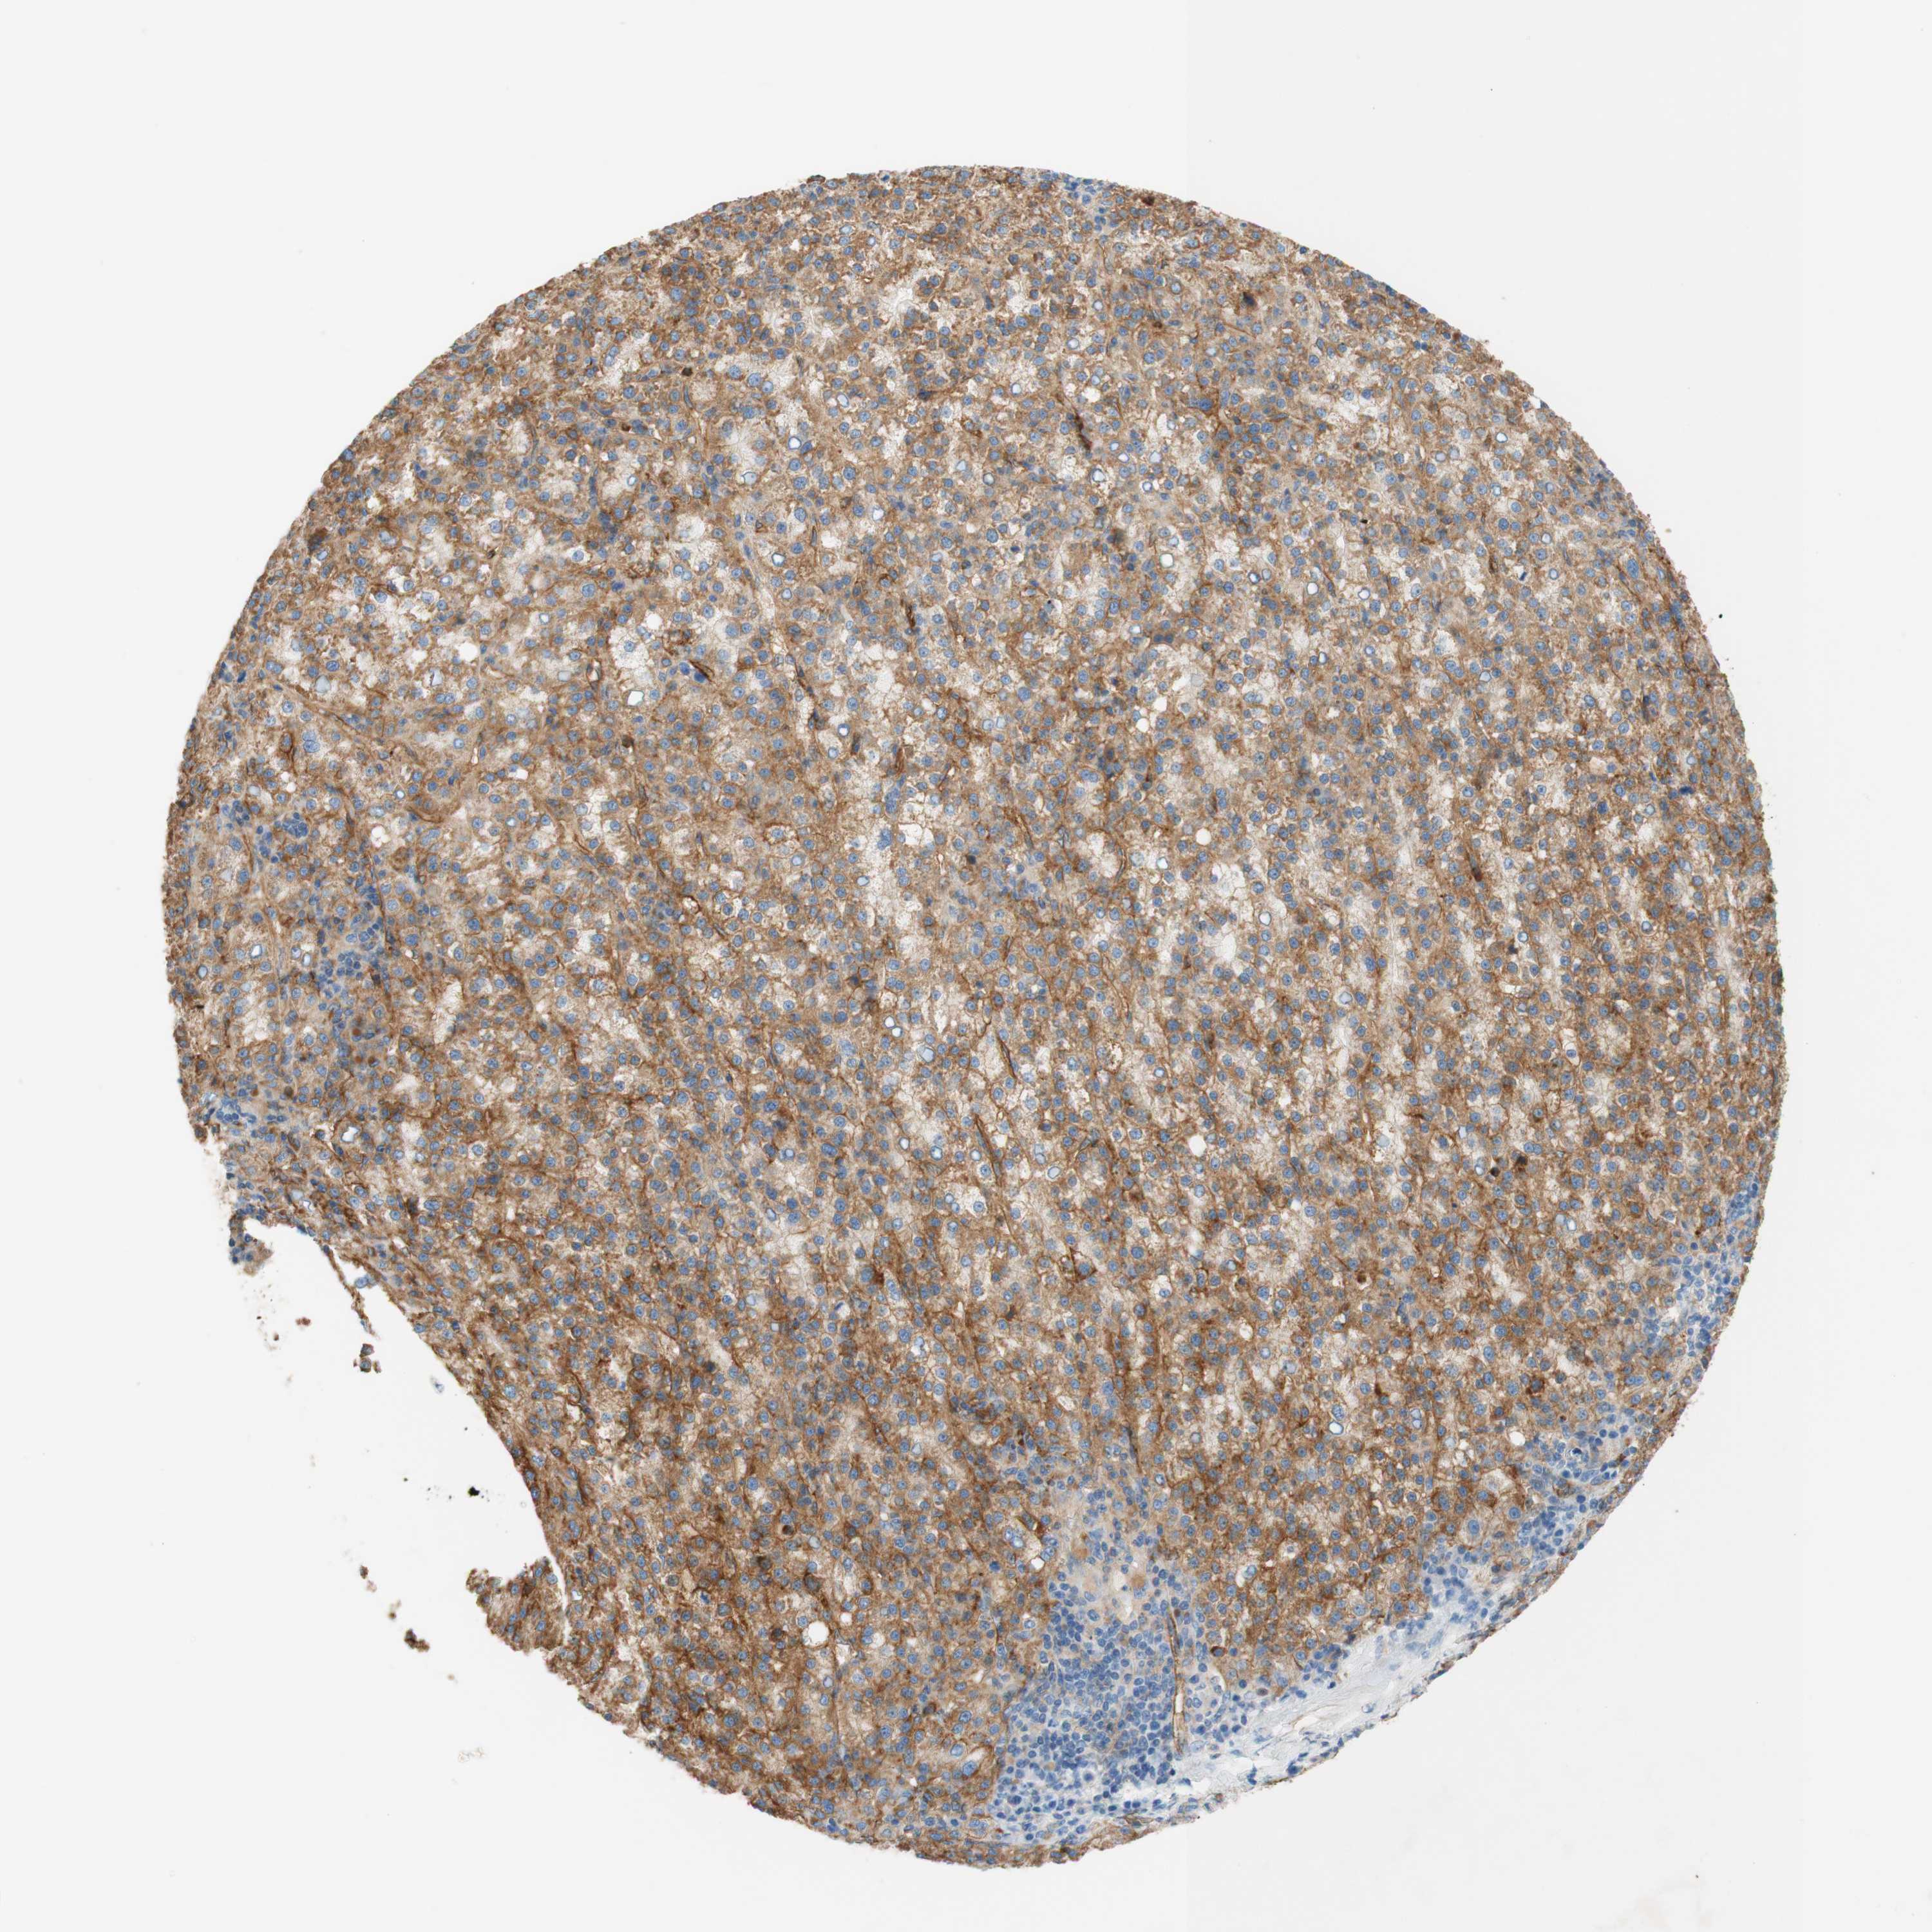

LIVER CANCER - Protein expressioni

A mouse-over function shows sample information and annotation data. Click on an image to view it in a full screen mode. Samples can be filtered based on level of antibody staining by selecting one or several of the following categories: high, medium, low and not detected. The assay and annotation is described here.

Note that samples used for immunohistochemistry by the Human Protein Atlas do not correspond to samples in the TCGA dataset.

Antibody stainingi

Antibody staining in the annotated cell types in the current human tissue is reported as not detected, low, medium, or high, based on conventional immunohistochemistry profiling in selected tissues. This score is based on the combination of the staining intensity and fraction of stained cells.

Each image is clickable and will lead to virtual microscopy that enables deeper exploration of all samples and also displays staining intensity scores, fraction scores and subcellular localization as well as patient and tissue information for each sample.

Antibody HPA010961

Antibody HPA011419

Staining

High

Medium

Low

Not detected

Intensity

Strong

Moderate

Weak

Negative

Quantity

>75%

75%-25%

<25%

None

Location

Nuclear

Cytoplasmic/membranous

Cytoplasmic/membranous,nuclear

Cholangiocarcinoma

Carcinoma, Hepatocellular, NOS